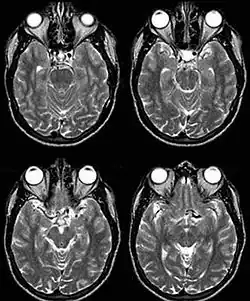

Fig. 1: Dolichoectasia of the suprasellar segment of the left internal carotid artery with compression of the optic chiasm

Internal carotid artery dolichoectasia is particularly interesting because the artery normally already contains one hairpin turn. Seen in an MRI as two individual arteries at this hairpin, a carotid artery dolichoectasia can progress so far as to produce a second hairpin turn and appear as three individual arteries on an MRI. In the case of a dolichoectasia of the Internal Carotid Artery (ICD), the pathogenesis is primarily related to compression of the optic nerves at the optic chiasma (see Fig. 1 and 2).